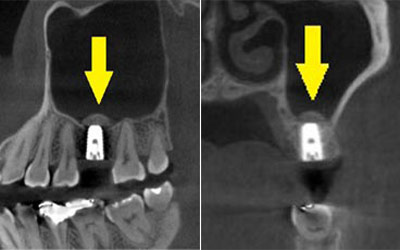

患者様のインプラント治療前のレントゲン写真です。右下顎大臼歯2本の抜歯後のレントゲン写真で、写真の黄色矢印は、歯の周囲の歯槽骨が大きく吸収されてしまっていました。

写真のように、CTで見ると、骨吸収の様子が良く分かり、下顎骨の中を通る神経近くまで骨がありませんでした。

さらに、CTで、別な方向から見ると、黄色矢印のように骨が吸収されていて、緑色矢印で示される神経の通る管に迫り、インプラントが埋入できるような骨量はありませんでした。

インプラントを埋入するために、骨を増やす方法はいくつかありましたが、この場合、患者様ご自身の骨をブロック状で移植するのが最も適していると判断し、自家骨移植術を行ないました。患者様ご自身の下顎前歯の下方から骨を採取して、骨がなかった部位に移植し、スクリューで固定したCT画像です。黄色矢印部分が、2つの骨片を移植して、固定したところです。

手術後の、別な方向からみたCT画像です。術前に大きく吸収されていた部分に、骨のブロックが移植され、骨が造成されています。真っ白にピンのように写るのは、骨を固定した小さなスクリューです。

移植した骨が周囲の骨と、結合したのを待ち、6か月後に、インプラント埋入手術を行いました。下の写真が、インプラント埋入後のCT画像で、黄色矢印に示すように、インプラントが2本埋入できました。

インプラント埋入後の、別な方向からみたCT画像です。神経の通る管にややギリギリでしたが、神経は傷つけずに、インプラントが埋入できました。この後、4か月ほどで、咬む歯の部分、上部構造を完成させました。